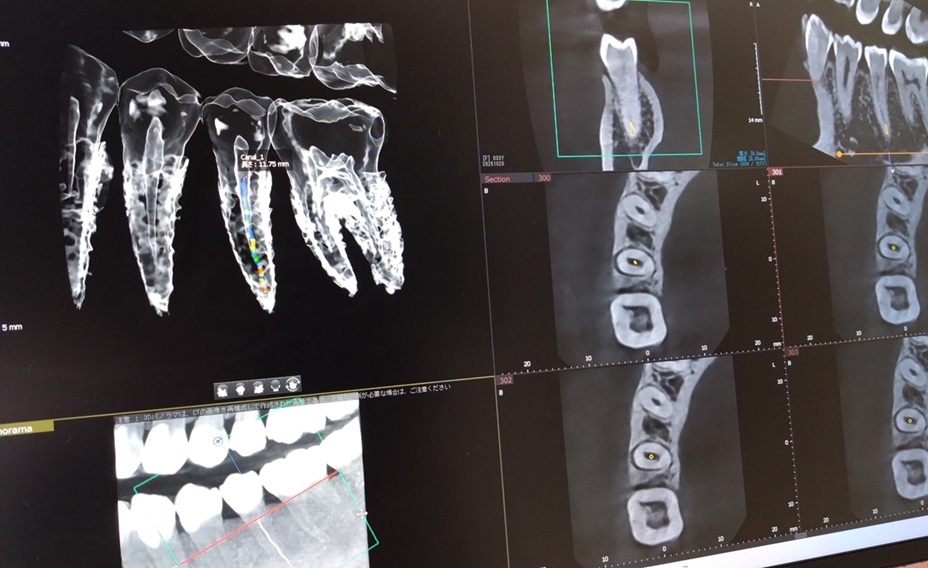

「精密根管治療」 あまり聞きなじみのない言葉かもしれませんが、歯科の治療では土台となる非常に重...

当院ではかねてより医科用のCT撮影を外部に依頼しておりましたが、本日当院にて高精度のCT撮影が...